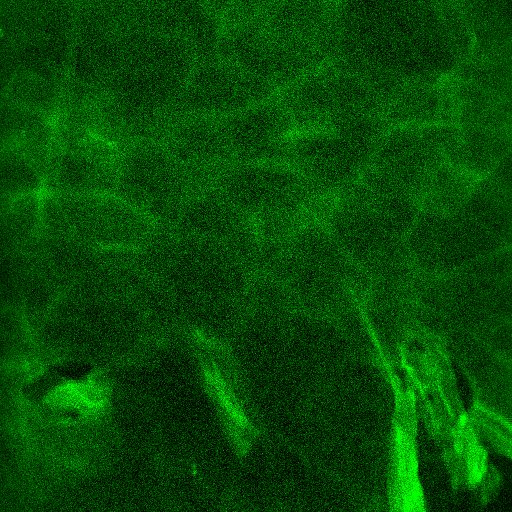

图5. 真皮层弹性纤维:在基底细胞层下方观察到,呈网状结构,采集时需注意到达此层若出现毛囊空洞需重新采集

图6. 真皮层胶原纤维:纹理结构,呈现条带状或网状,采集时需注意到达此层若出现毛囊空洞需重新采集(以上双光子图源来自CIRS化妆品功效临床评价实验室)